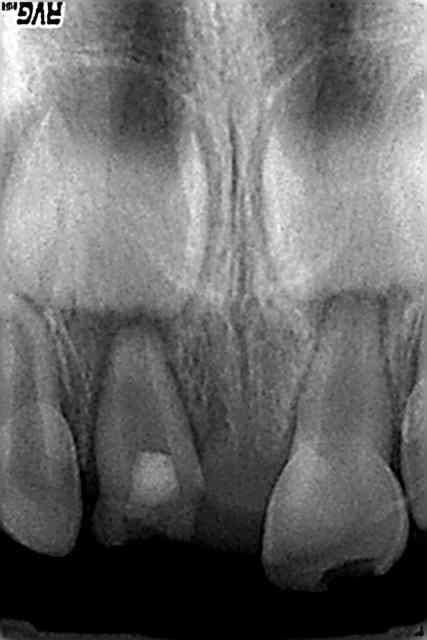

patiente vue en urgence decembre 2009, obturation + reconstitution + prov,revue une semaine après,plus de douleurs,fistule en voie de disparition

en fevrier RAS bien que l'image n'ait pas disparu(en 2 mois c'est impossible)

pose de la ceramique fin fevrier

RAS depuis

attendre oui mais pas non plus trop longtemps(risque de desct prov ou si tu n'en as pas fait,réinfiltration ou fracture,etc... )